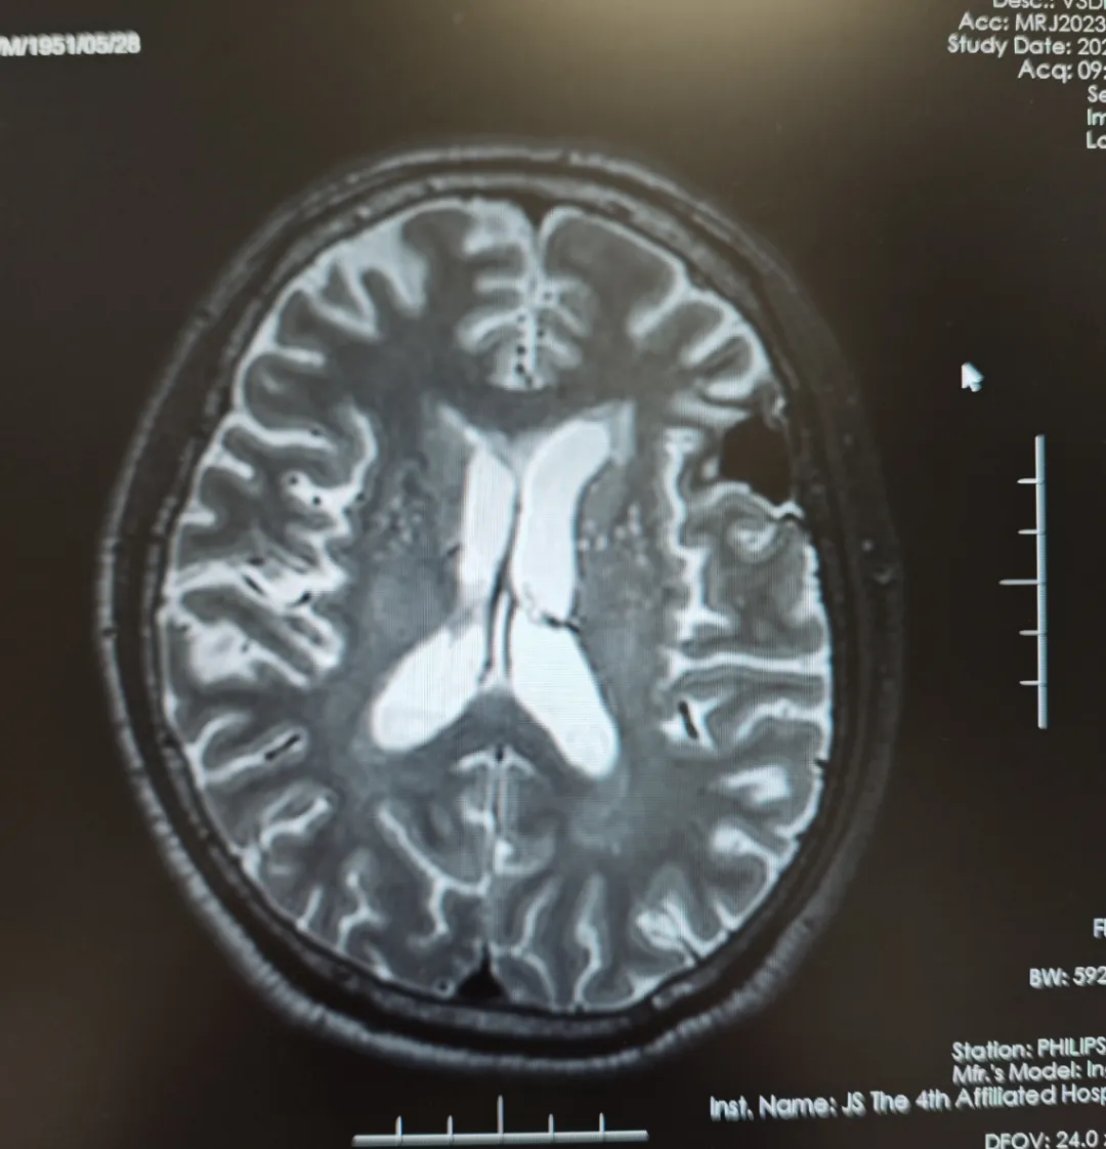

病情进展:2023年8月,患者出现头晕、行走不稳等神经系统症状。头部磁共振(MRI)检查证实了医生的担忧:左侧额叶出现了一个大小约3.8cm*3.2cm*3.5cm的占位性病变,诊断为小细胞肺癌脑转移瘤。

图1 脑转移确诊时磁共振影像